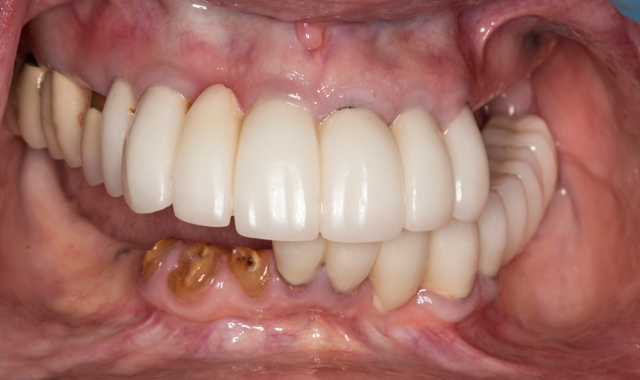

A 70-year-old patient presented with fractured teeth and multiple failing restorations (Fig. 1-2). It was determined that the mandibular teeth were not restorable. The treatment plan was for a mandibular fixed detachable prosthesis with five implants. Due to patient’s finances, the maxillary arch will be restored after the mandibular arch is finished.

Fig. 1

Fig. 2